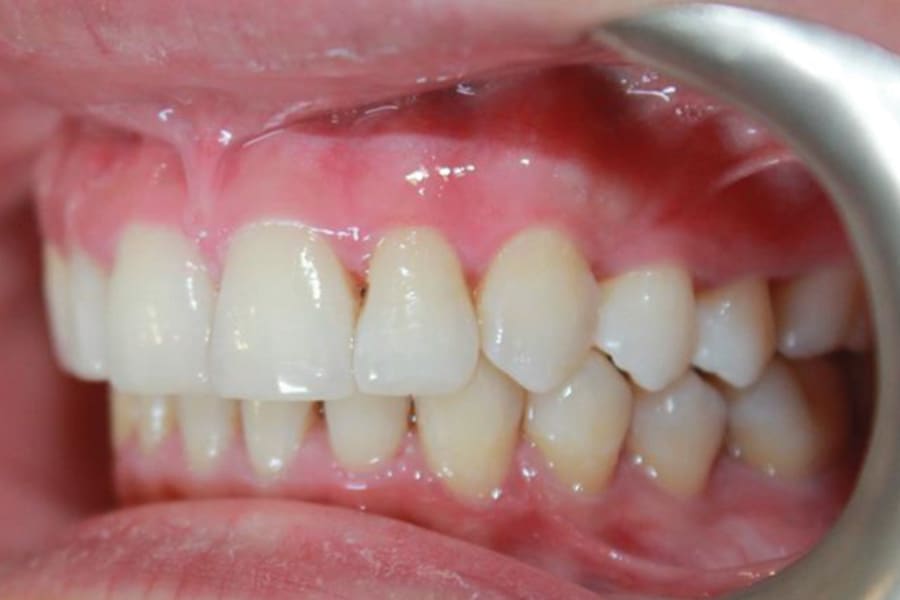

A 35-year-old woman presented with concerns of crowding, bruxism, and bite misalignment, which were associated with a class II malocclusion that would require a combination treatment of expansion, distalization, and molar derotation. ClearCorrect® aligner therapy (Straumann, clearcorrect.com) was selected as the primary modality, as the patient requested a non-invasive, esthetic treatment. The treatment plan was designed to be completed within 6 months of active aligner therapy. Class II elastics were prescribed, and the ClearCorrect FLEX case plan was chosen to allow for refinements, as needed. After comprehensive digital records were taken, the first set of aligners was delivered, engagers were bonded, and the patient was instructed to wear aligners on a 14-day cycle with full-time class II elastic wear. To enhance efficiency, more engagers were placed, including posterior attachments, to maximize control over molar distalization and anchorage. Interproximal reduction of 0.3 mm was performed in a few contacts at the initial appointment to facilitate space closure and alignment. Due to the complexity of the correction and the patient’s history of bruxism, a lower 3-3 bonded retainer was placed, and retainers were fabricated for both arches. The patient expressed a high level of satisfaction with the ClearCorrect aligner therapy, noting the comfort and esthetics of the aligners and the ability to achieve a fully corrected class II occlusion in just 6 months of treatment.